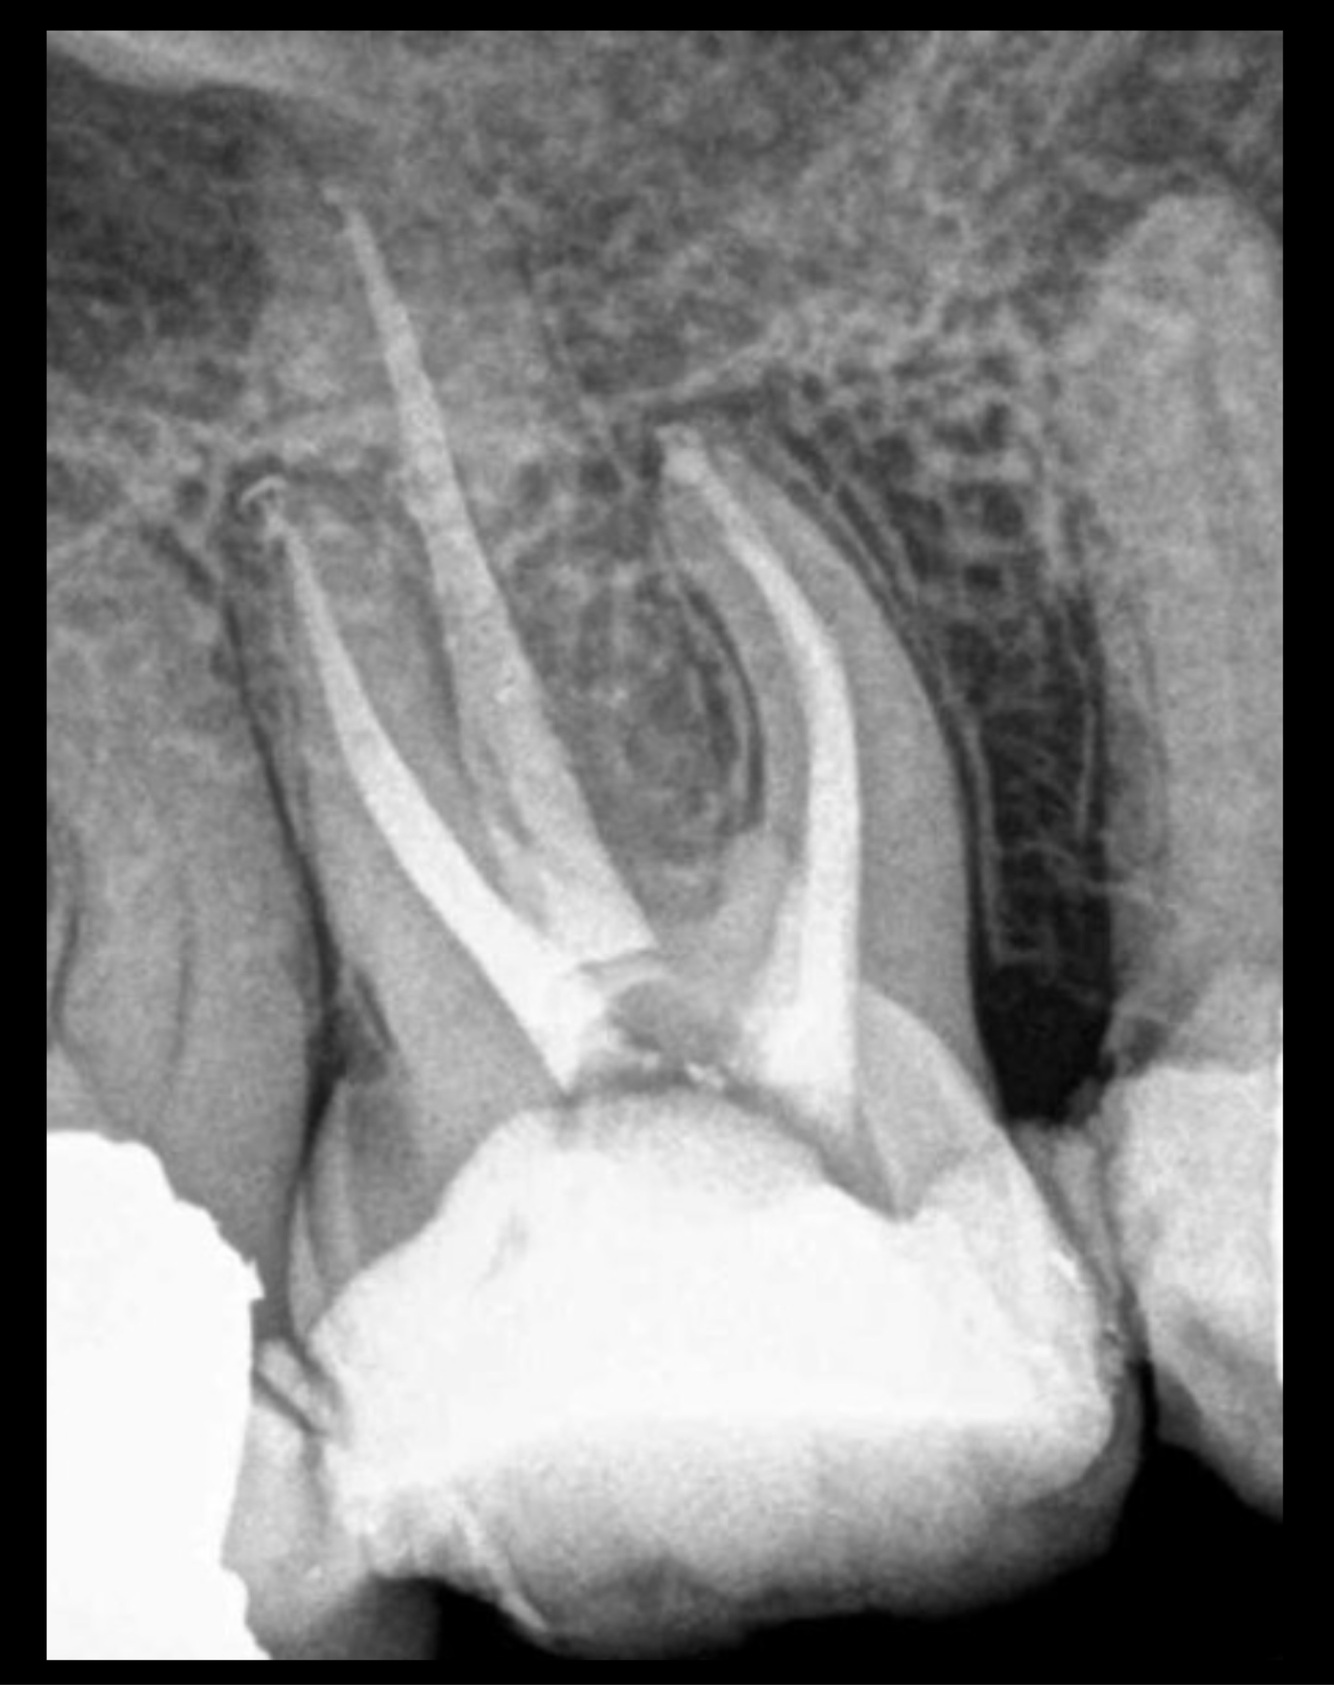

3

Q

The RCT done on:

Upper premolar

Upper molar

Lower premolar

Lower molar

A

4

13

14

17